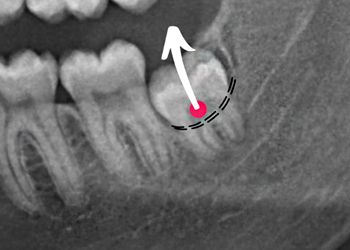

20 MODULES TO MASTER EXODONTIA

Everything you will ever need to know to master exodontia!